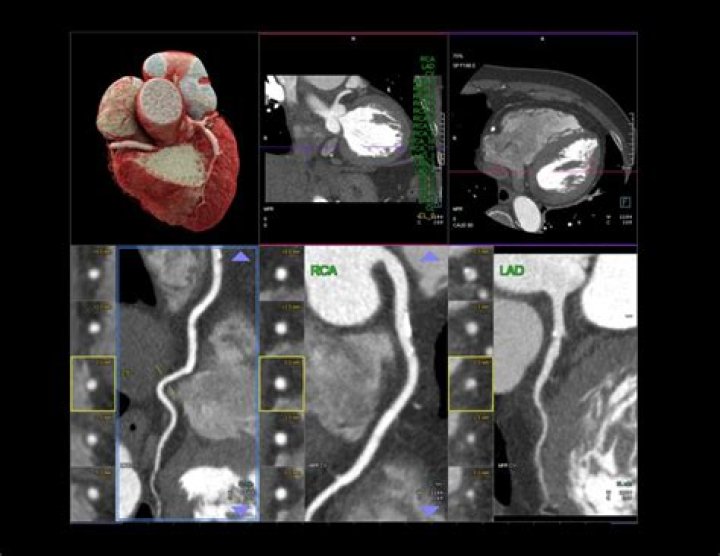

Can a heart CT scan detect blocked arteries?

A CT coronary angiogram can reveal plaque buildup and identify blockages in the arteries, which can lead to a heart attack. Prior to the test, a contrast dye is injected into the arm to make the arteries more visible. The test typically takes 30 minutes to complete.

There are several types of CT scans used in the diagnosis of heart disease, including: Calcium-score screening heart scan. Coronary CT angiography (CTA) Total body CT scan.

A heart CT scan shows detailed images of your arteries, aorta, heart and valves, so that healthcare professionals can measure your heart health without an invasive or lengthy procedure. After your heart CT scan in our low-dose Siemens CT scanner, you will receive your coronary calcium score.

What is the difference between a CT scan and a CT angiogram?